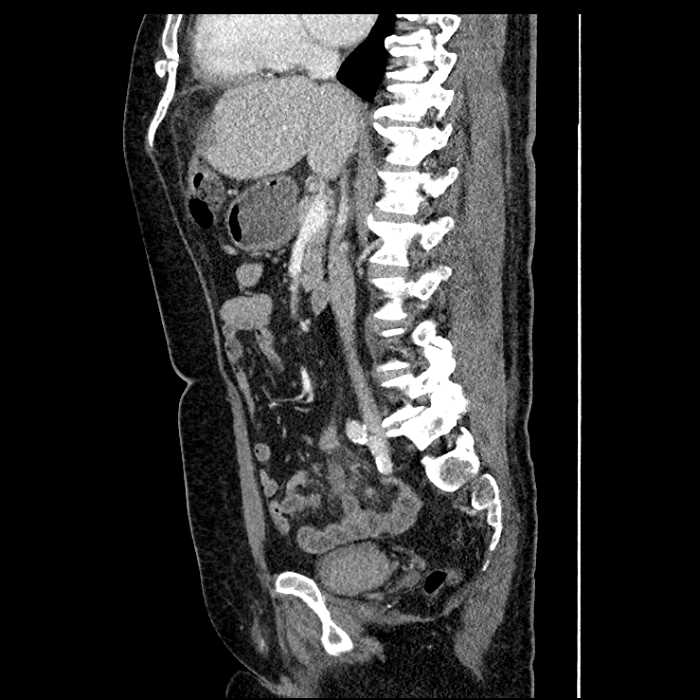

• Large fluid density structure in hepatic segments 7 and 8 measuring 10 x 7 x 7 cm with internal septation and circumferential ill-defined low density compatible with edema

• Peripherally enhancing subcapsular collections along the anterior margin of the left hepatic lobe measuring 3 x 1 cm and 2 x 1 cm

Acute sigmoid diverticulitis complicated by a small contained perforation and a large abscess in the right hepatic lobe. Additional small subcapsular abscesses along the anterior margin of the left hepatic lobe.

Additionally, loss of the normal fat plane between the peridiverticular collection and adjacent thickened loops of small bowel raises the potential for an enterocolonic fistula.

• The classic CT imaging appearance is a double target sign with internal low density surrounded by an internal enhancing rim (capsule) and a low density external rim (edema)

Hepatic abscess showing the double target sign with low density internally surrounded by a thin inner enhancing rim (red arrow) and ill-defined outer low density rim (yellow arrow). Blue arrow indicates an internal septation. Red arrows: additional smaller subcapsular abscesses. Red arrow: focal contained perforation associated with diverticulitis.